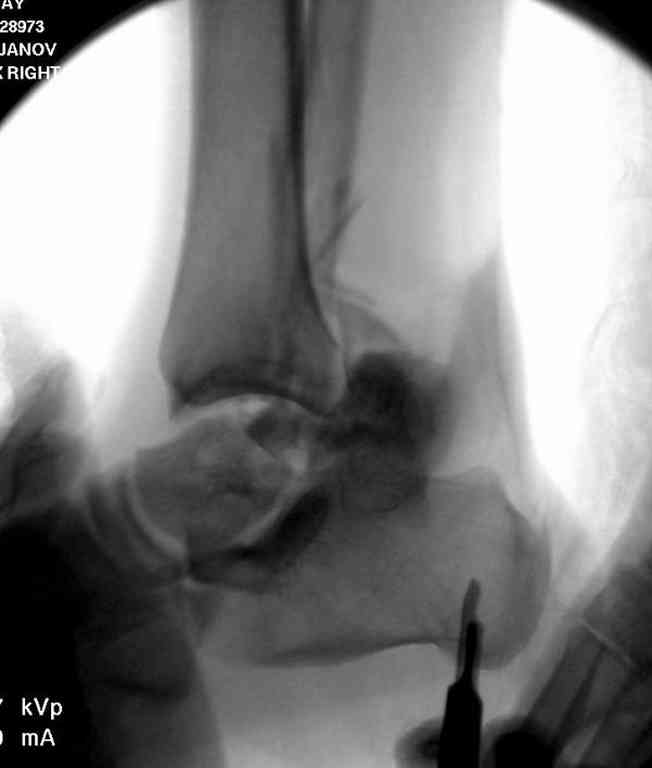

Прошу коллег помочь советом.3 дня назад поступила пациентка 23 года с переломом шейки ладьевидной справа, переломом лодыжек и заднего края б/берцовой кости со смещением и подвывихом кзади, переломом внутреннего мыщелка правого бедра без смещения. Дежурными хирургами проведена репозиция в левом г/ст суставе успешная, попытка репозиции таранной кости ухудшило положение отломков. Планируем провести повторную репозицию и фиксацию винтами. 1. Закрытая репозиция рентгенконтоль интраоперационный (аппарат Арман) ификсация из заднее-наружного доступа. 2. При неудачной закрытой репозиции переходим на открытое вправление двумя доступами медиальным и латеральным "по ходу оси таранной кости" и через дополнительный задний доступ вводим винты кортикальные 4,5 мм или 3,5 мм 3. после открытой репозиции фиксация двумя винтами через боковые доступы погружая их под суставную поверхность Сергей Зырянов ЦРБ Новосибирская область

Здесь на фото примеры:

Переломовывих тарана с повреждением медиальной стороны. Через 4 часа после поступления проведена репозиция и фиксация тарана после Irrigation&Debridment. Частичное несращение медиальной лодыжки не беспокоит, вернулся к активному образу жизни. Полная нагрузка разрешена через 11 недель. Финальные снимки через 11 месяцев.